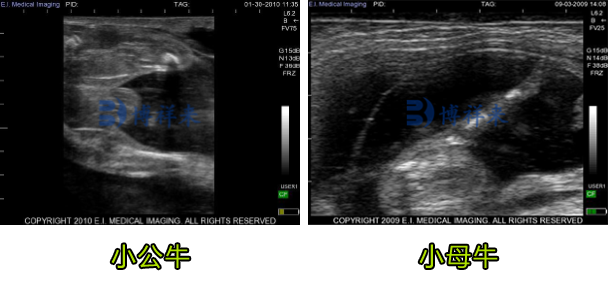

随着妊娠进入 60 – 90 天,受超声设备频率和穿透深度的影响,子宫内胎儿骨骼、羊膜和胎盘结构更易成像,此阶段可以判断胎儿公母:

约 60 天:胎儿体长较明显,可以测量不同部位(如身体长度、双顶径等)来科学估算妊娠天数。

90 天左右:骨骼钙化程度加强,骨影在图像中呈高回声线条,脐带、胎盘结构也越来越清晰。此阶段 B 超图像能够提供较精准的胎龄估算基础。